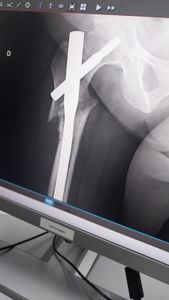

sofri uma tentativa de homicídio aonde tentaram contra a minha vida, tenho meus filhos pequenos sou mãe solo, no momento não tenho como arcar com as custas do hospital aonde irei precisar refazer a cirurgia do fêmur com URGÊNCIA.

Preciso muito dessa cirurgia para voltar a andar venho pedir encarecidamente de todo coração que me ajudem a arcar com as custas do hospital irei precisar faser uma cirurgia para voltar a andar, uma cirurgia um pouco invasiva aonde preciso retirar um pedacinho de osso da Bacia para repor no osso do fêmur.